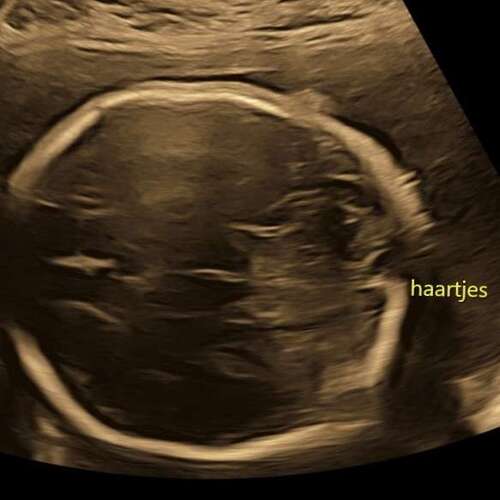

Dit is onze beauty op de echo met haartjes maar is dus nog even afwachten! 30/8 is de uiterekende datum!